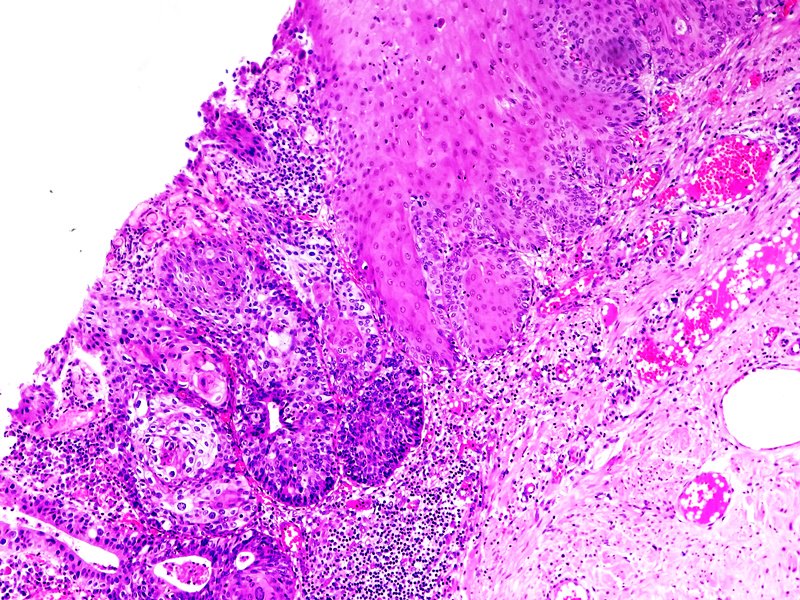

Cérvix uterino. Zona de transformación con carcinoma epidermoide in situ. Tinción HE